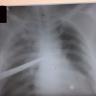

Chest trauma can present in many unique and unusual ways, but, if managed in time, patients can have an excellent prognosis. This video shows three cases of chest trauma with different modes of injury and varied presentations.